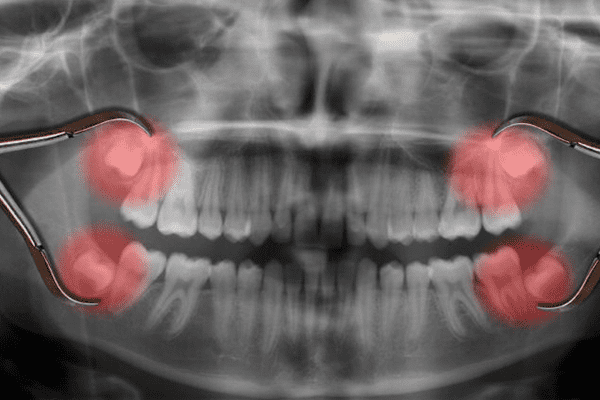

Dental Clinic in Narasimhanaickenpalayam

At GuGu Dental Clinics, we take delight in being one of the most trusted dental clinics in Narasimhanaickenpalayam, supplying whole oral care for the complete own family. From routine checkups to advanced dental treatments, our team of professional dentists ensures that every patient gets personalized and extremely good care.